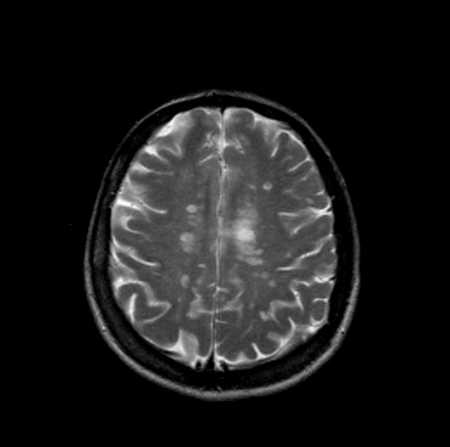

Информация о диссеминированном рассеянном энцефаломиелите